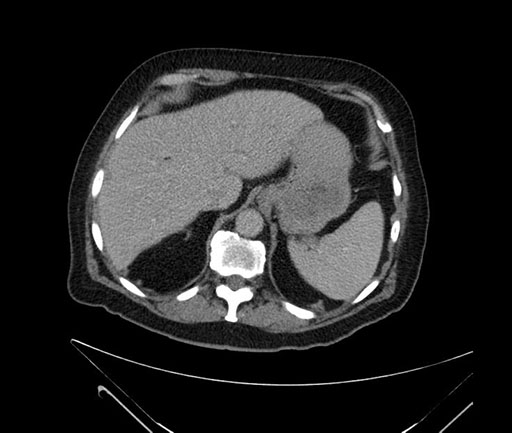

Whipple (pancreaticoduodenectomy) [case 7]

Imaging Analysis

Look through the patient's CT scan to identify any areas of concern for the necessary procedure.

Axial - stented